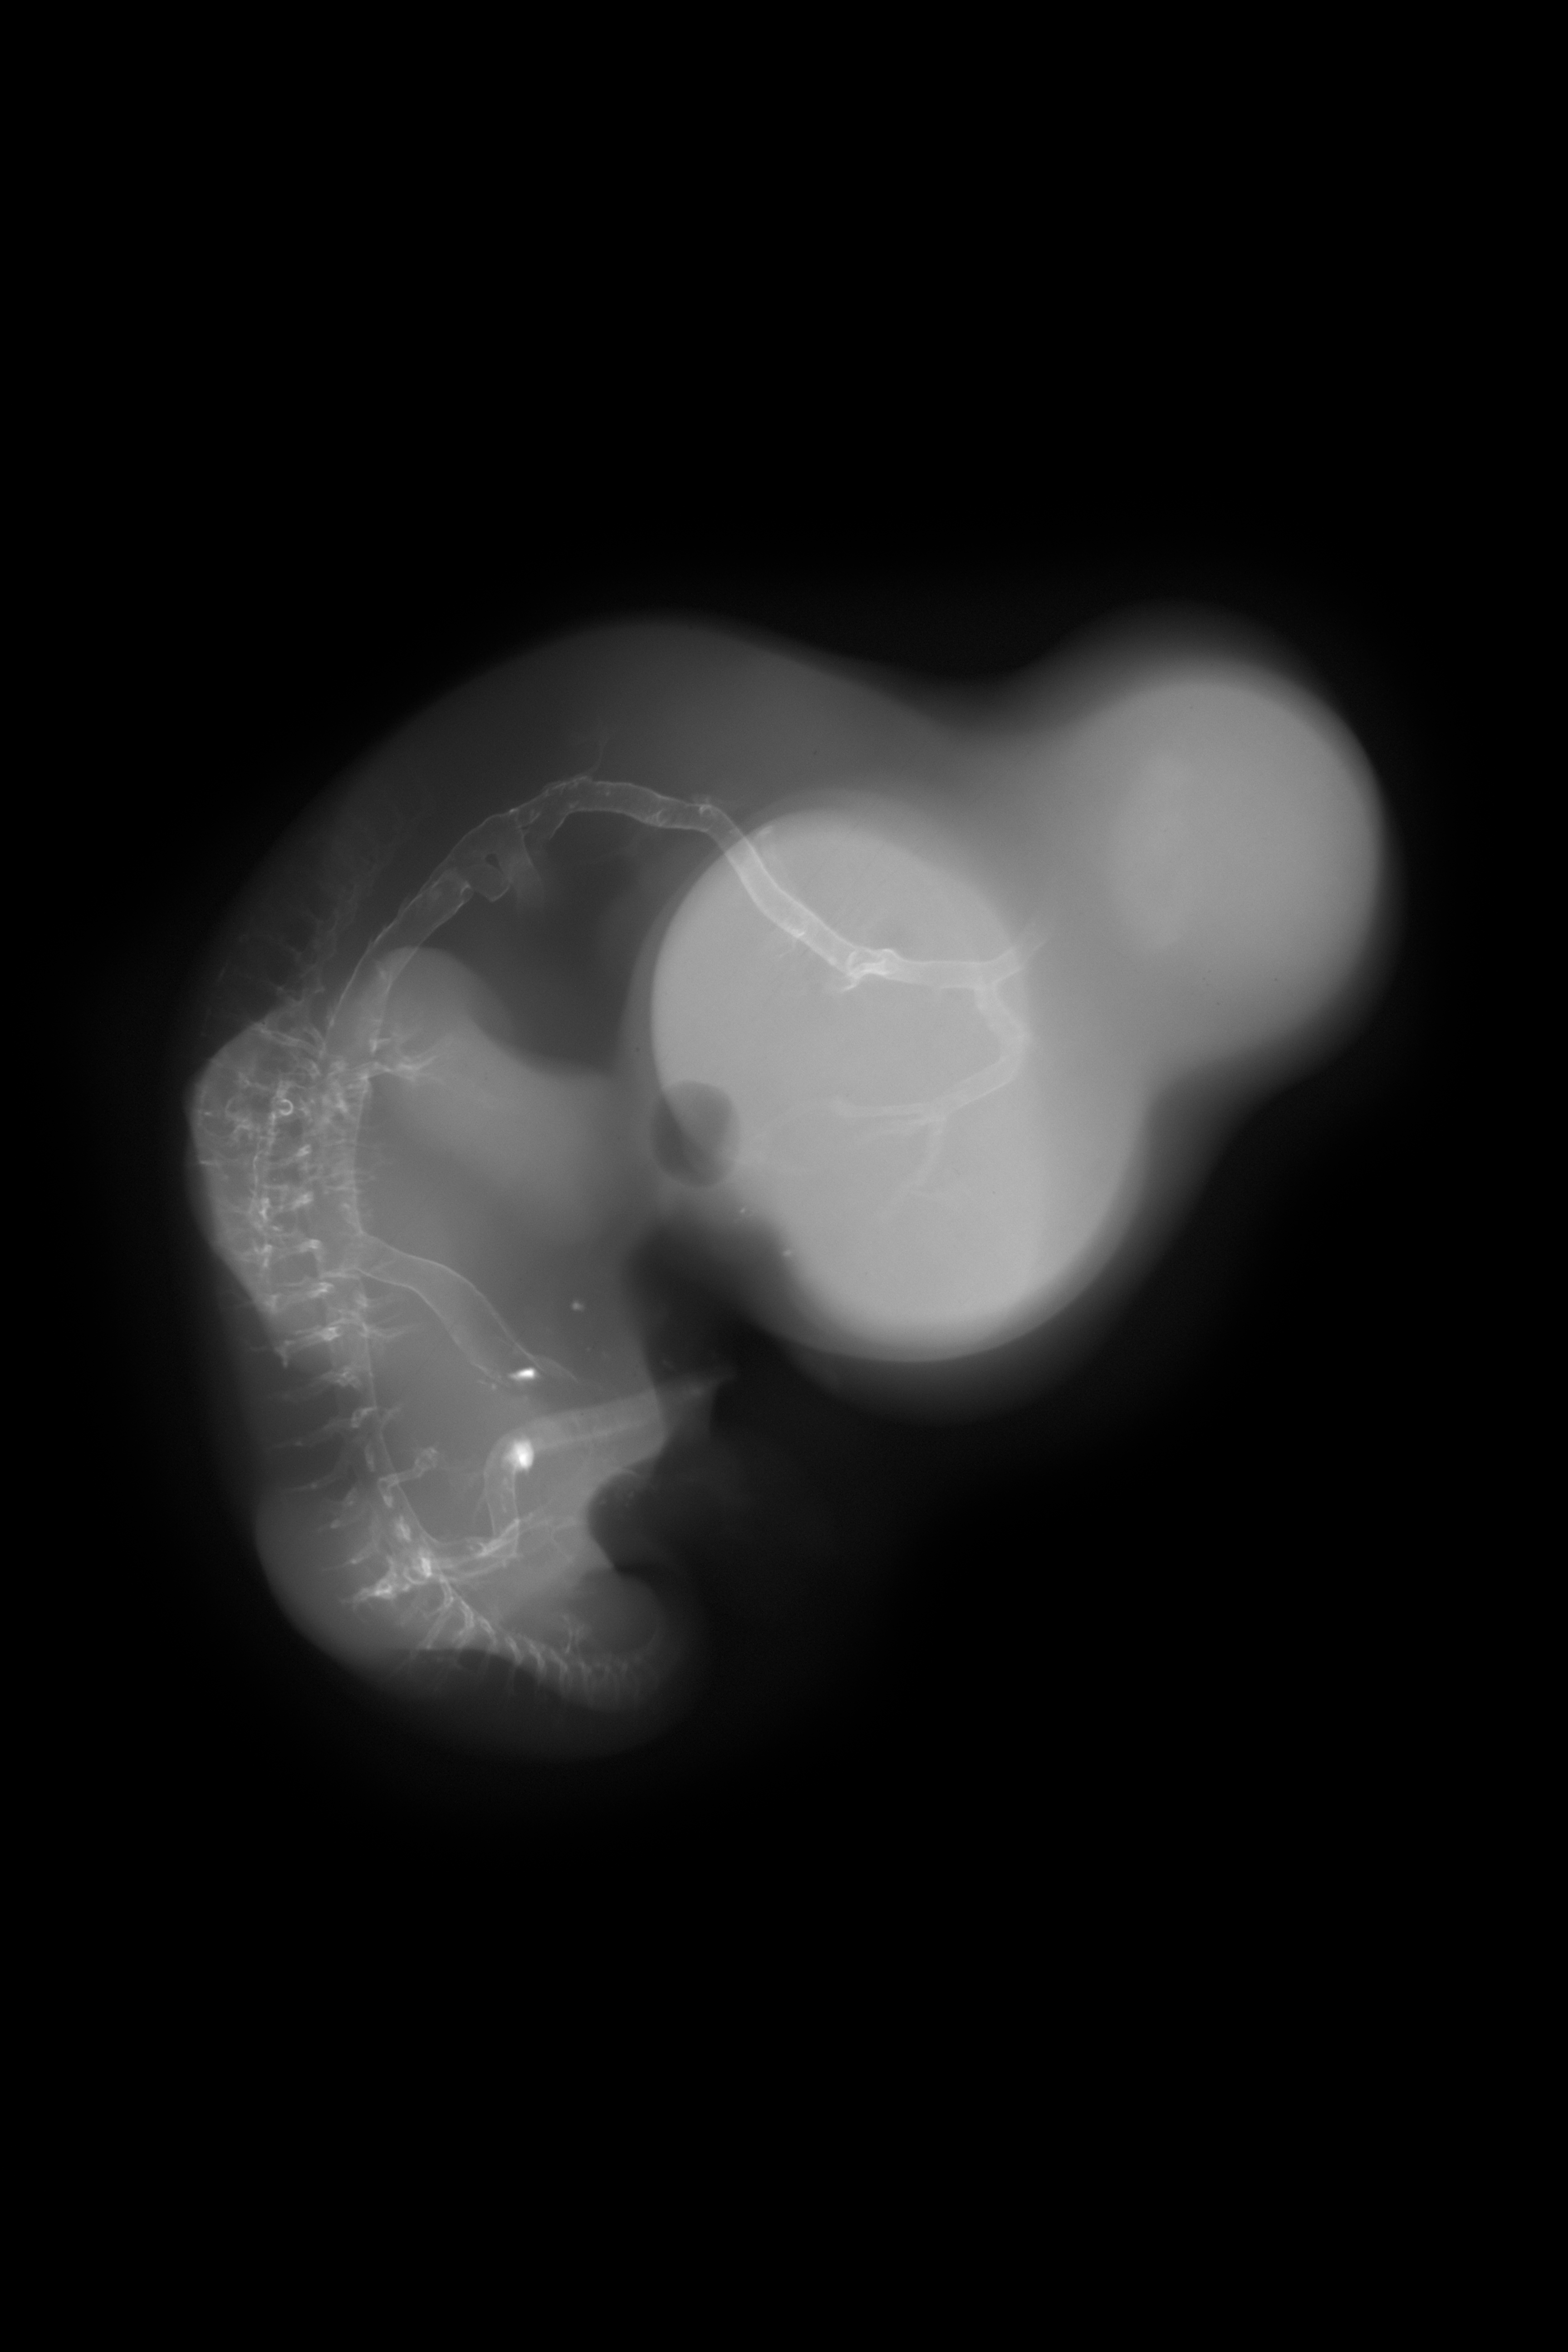

Drawing